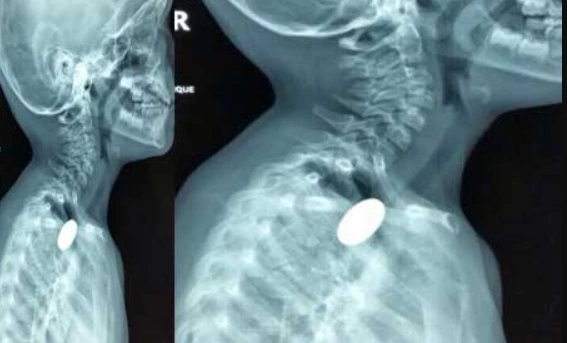

गले में फंसा सिक्का, सांसें अटक गईं… डॉक्टरों ने ऐसे बचाई 5 साल के बच्चे की जान

खेल-खेल में गले में फंसा ₹5 का सिक्का, सिम्स के डॉक्टरों ने बिना ऑपरेशन मासूम को दी नई जिंदगी-छत्तीसगढ़ के बिलासपुर स्थित सिम्स अस्पताल के डॉक्टरों ने एक बार फिर अपनी काबिलियत साबित की है। एक 5 साल के मासूम के गले में फंसा सिक्का बिना किसी चीर-फाड़ के आधुनिक तकनीक से निकाल लिया गया। डॉक्टरों की सूझबूझ और टीमवर्क ने न सिर्फ बच्चे की जान बचाई, बल्कि सरकारी अस्पताल के प्रति जनता का भरोसा भी बढ़ाया है।

खेलते-खेलते हुआ हादसा, अटक गई बच्चे की सांसें-छत्तीसगढ़ के चिरमिरी के रहने वाले 5 साल के मासूम नितिन सिंह के साथ खेलते वक्त एक दर्दनाक हादसा हो गया। खेल-खेल में उसने ₹5 का सिक्का निगल लिया, जो सीधे उसके गले में जाकर फंस गया। इसके बाद बच्चे को सांस लेने में भारी तकलीफ होने लगी और उसकी हालत नाजुक हो गई।

एंडोस्कोपी का जादू: बिना चीरे के बाहर आया सिक्का-डॉक्टरों ने बच्चे के गले से सिक्का निकालने के लिए आधुनिक ‘एंडोस्कोपिक तकनीक’ का सहारा लिया। इस प्रक्रिया की सबसे अच्छी बात यह रही कि बच्चे के शरीर पर कहीं भी कोई बड़ा चीरा या टांका नहीं लगाना पड़ा। विशेष उपकरणों की मदद से डॉक्टरों ने बहुत ही सावधानी से सिक्के को बाहर निकाल लिया।